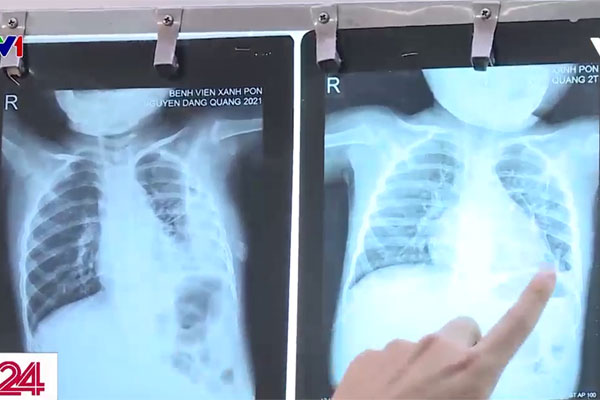

Chị Đỗ Thảo Ly, TP. Hà Nội cho biết: "Chụp phim đã bị mưng mủ trắng hết bên phổi rồi. Chỉ có 2 nốt thôi rất to nên không biết cách điều trị như nào".